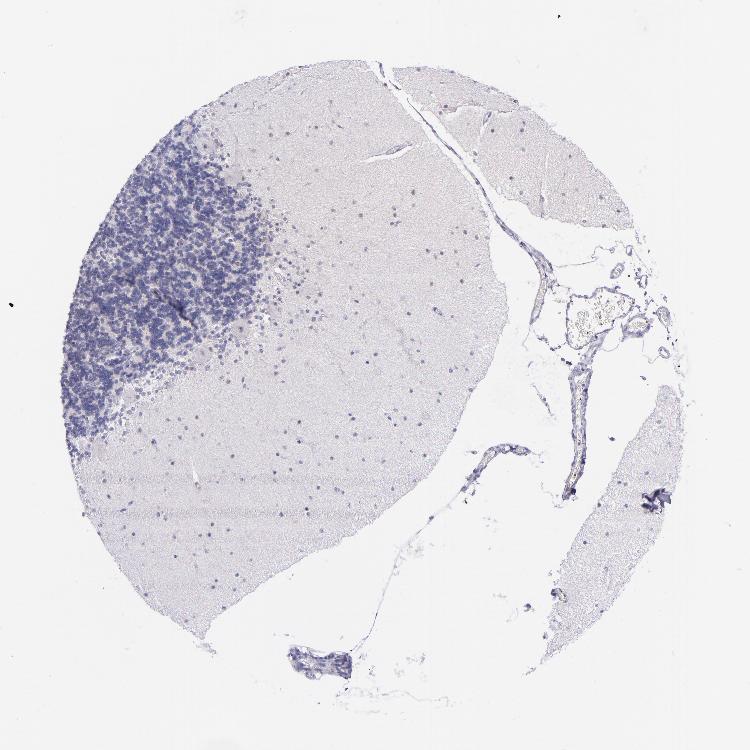

CEREBELLUM - Antibody stainingi

Antibody staining in the annotated cell types in the current human tissue is reported as not detected, low, medium, or high, based on conventional immunohistochemistry profiling in selected tissues. This score is based on the combination of the staining intensity and fraction of stained cells.

Each image is clickable and will lead to virtual microscopy that enables deeper exploration of all samples and also displays staining intensity scores, fraction scores and subcellular localization as well as patient and tissue information for each sample.

Antibody CAB002143

Purkinje cells Not detected

Cells in granular layer Not detected

Cells in molecular layer Not detected